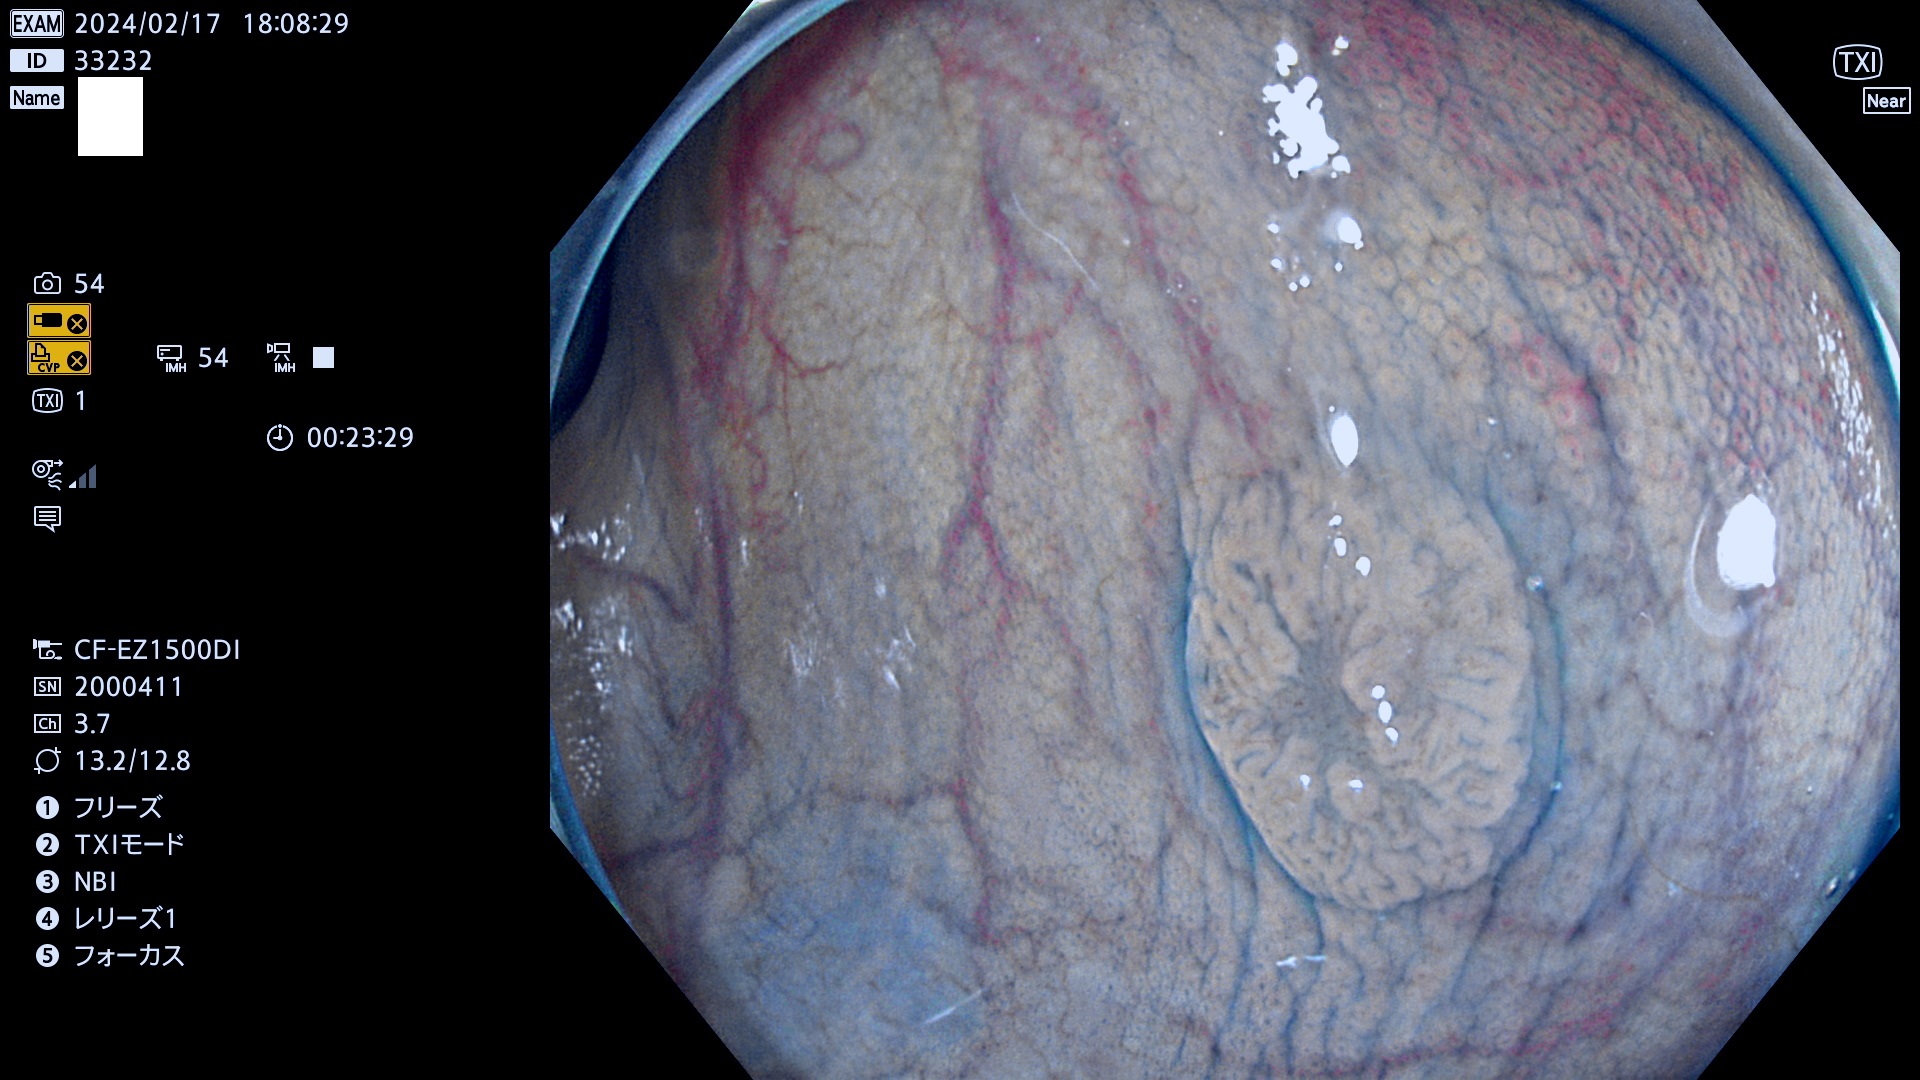

今週のUb、Uc型腺腫

表面型腺腫(Flat Adenoma)の中で、完全に平坦な物をUb、陥凹している物をUcと呼びます。平坦隆起型(Ua)よりも、発見が難しく危険な病変です。

毎週の検査(木・金・土・日)に発見されたUb、Uc型・腺腫を、その週の日曜の夜にUPし1週間、提示します。

抽出の対象期間 2024年2月15日(木)〜2月18(日)の4日間(40件の検査)10件 (10/40=25%)